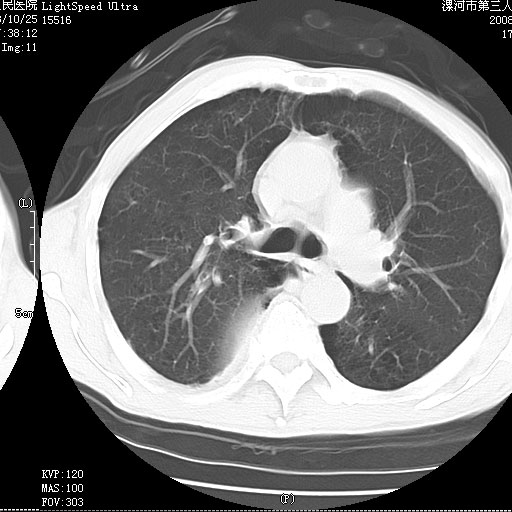

应该是脓胸的表现,右下肺气管阻塞考虑为痰栓.

你怀疑的有道理,慢支、肺气肿、肺打泡是有了,右下肺的病变有待商议;

首先考虑右下肺炎症并不张,不除外早期肺泡癌改变

病灶边缘清---多个含气小腔---近端未见通畅气管影-----支持-----慢性肺脓肿继发阻塞性肺不张

阻塞性肺不张原因-----脓液未排出